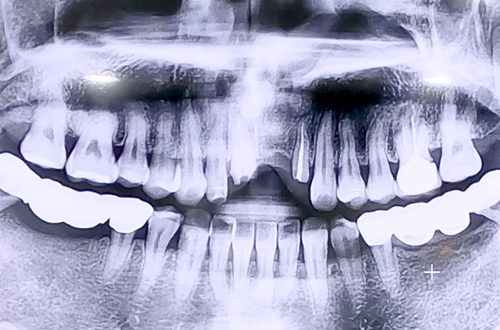

AFTER

앞니이기 때문에 임시치아를 제작하고 보철 부품을 끼워 마무리해 드렸습니다.

5개월 정도 임플란트가 단단히 자리 잡는 기간을 기다린 뒤 최종적으로 앞니 보철을 완성해 드릴 예정입니다.